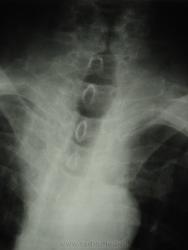

мужчина 1932 г.р. (лежачий пациент, инвалид) привезли со скорой на рентфию ОГК. случайно оказалась рядом и выяснила у сына, что он 3 дня не разговаривает и не кушает. Решила дать глоток бария пока лежит(снимки наспине), вот что получилось....

Образование или инородное тело?

С учетом таких контуров образования возможно лейомиома, но расположение странное, а может образование идет со стороны щитовидной железы?

наверно инородное тело врядли (большое какое то), может из щитовидки что то прорасло??? а может вообще заглоточный абсцесс????

Ну, у стариков инородное тело (кусок мяса) может дать интересные картинки.

Тоже на все 100% соглашаюсь с Валентином Львовичем, в первую очередь необходимо исключать т.н. "мясной завал", а мясо там...сало ...или еще что - дело десятое.....